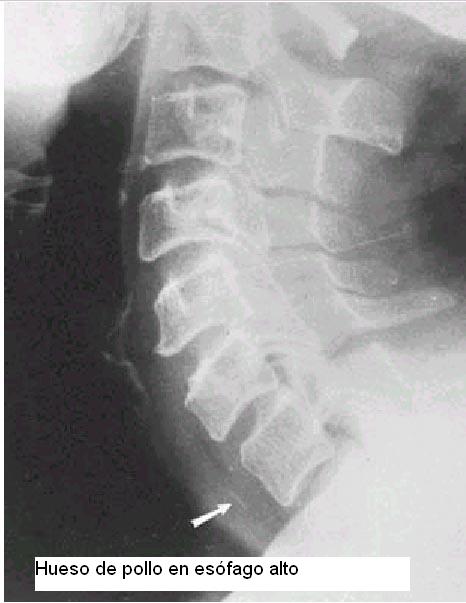

2) En adultos lo mas frecuente es huesos de pollo, espinas de pescado, carne en trozos mal masticados por mala dentición(en adultos mayores).

Rx simples de perfil de cuello con técnica para partes blandas en hiperextensión son de utilidad para objetos radio opacos.

Con un trago de bario si la rx simple sugiere un c/ extraño radio lúcido.

Manejo de cuerpos extraños de esófago:

1) Diagnóstico clínico-rx

2) Extracción por esofagoscopía rígida.